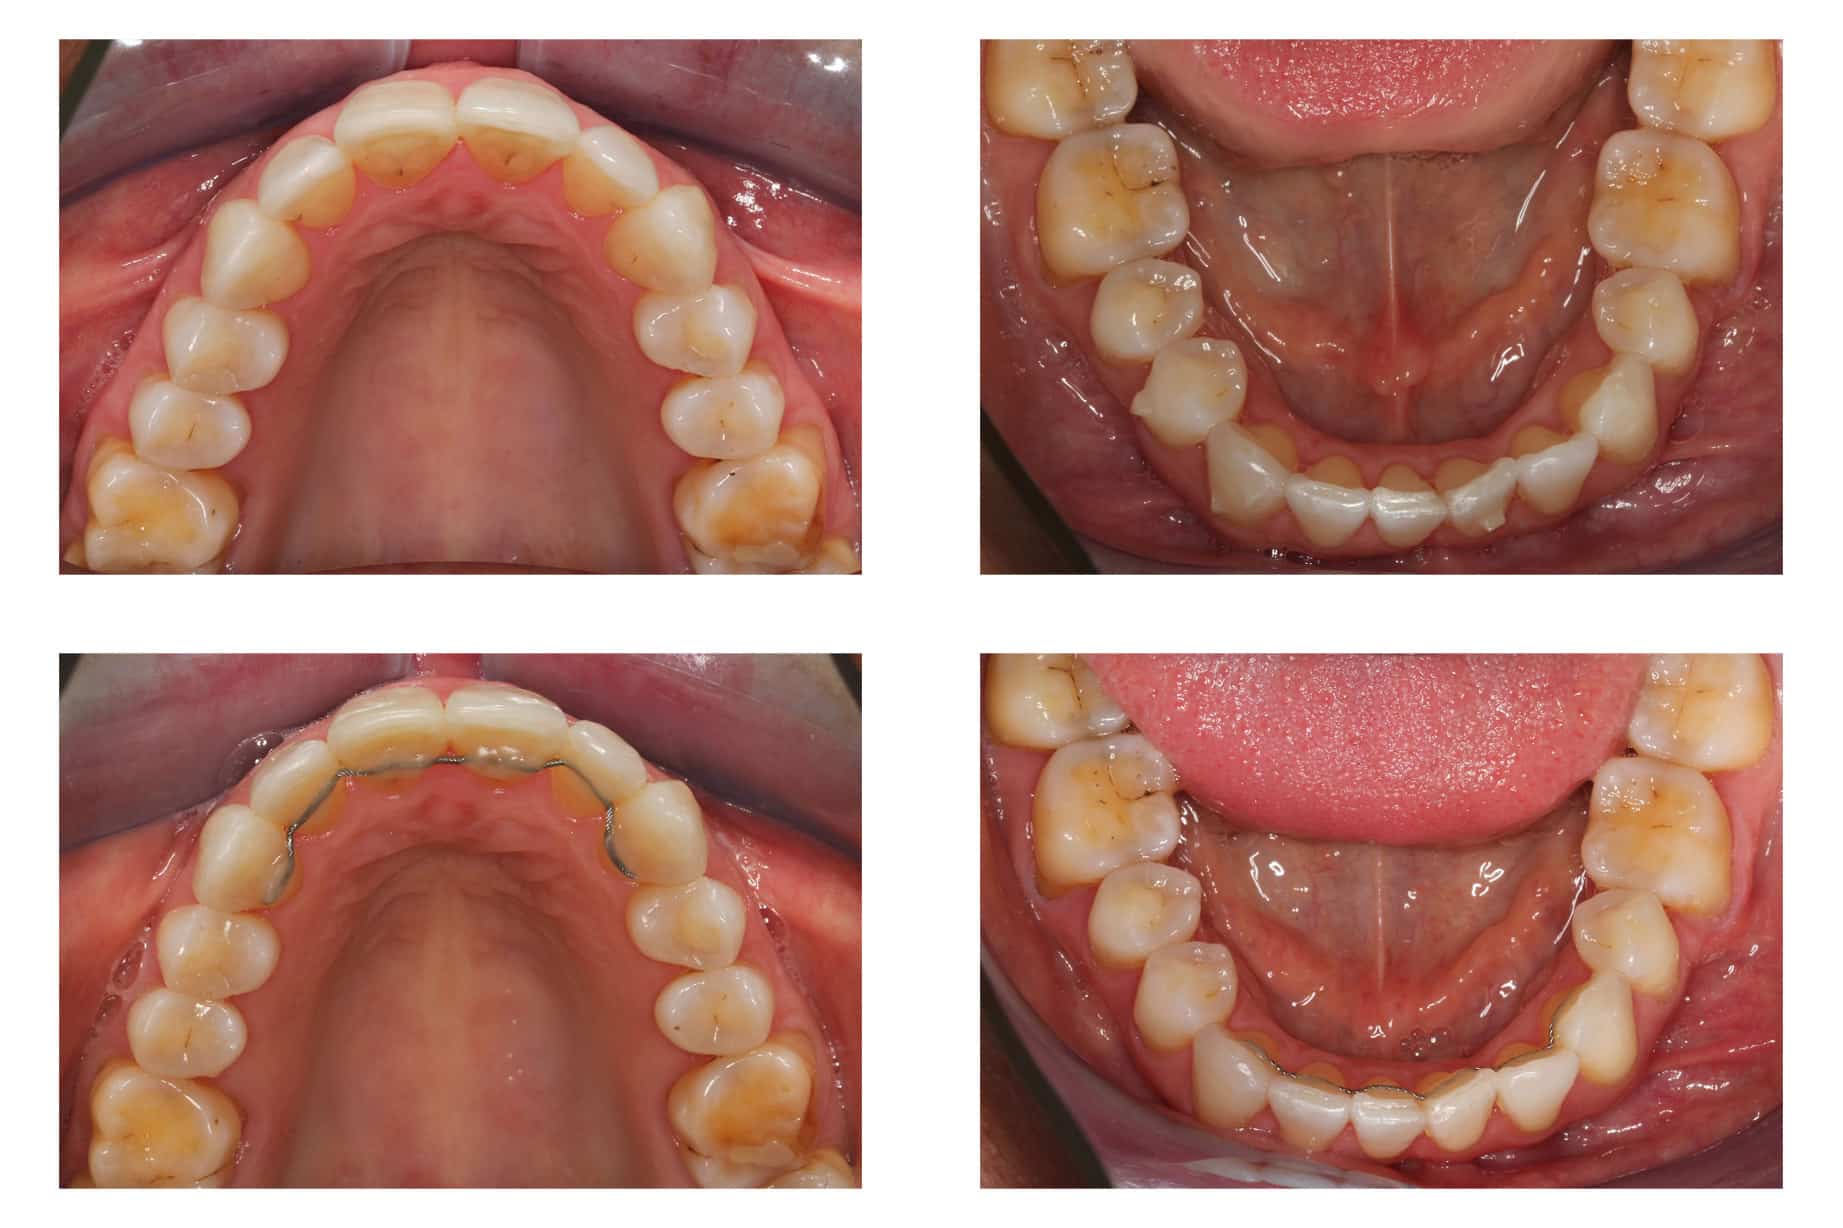

Før- og etterbilder